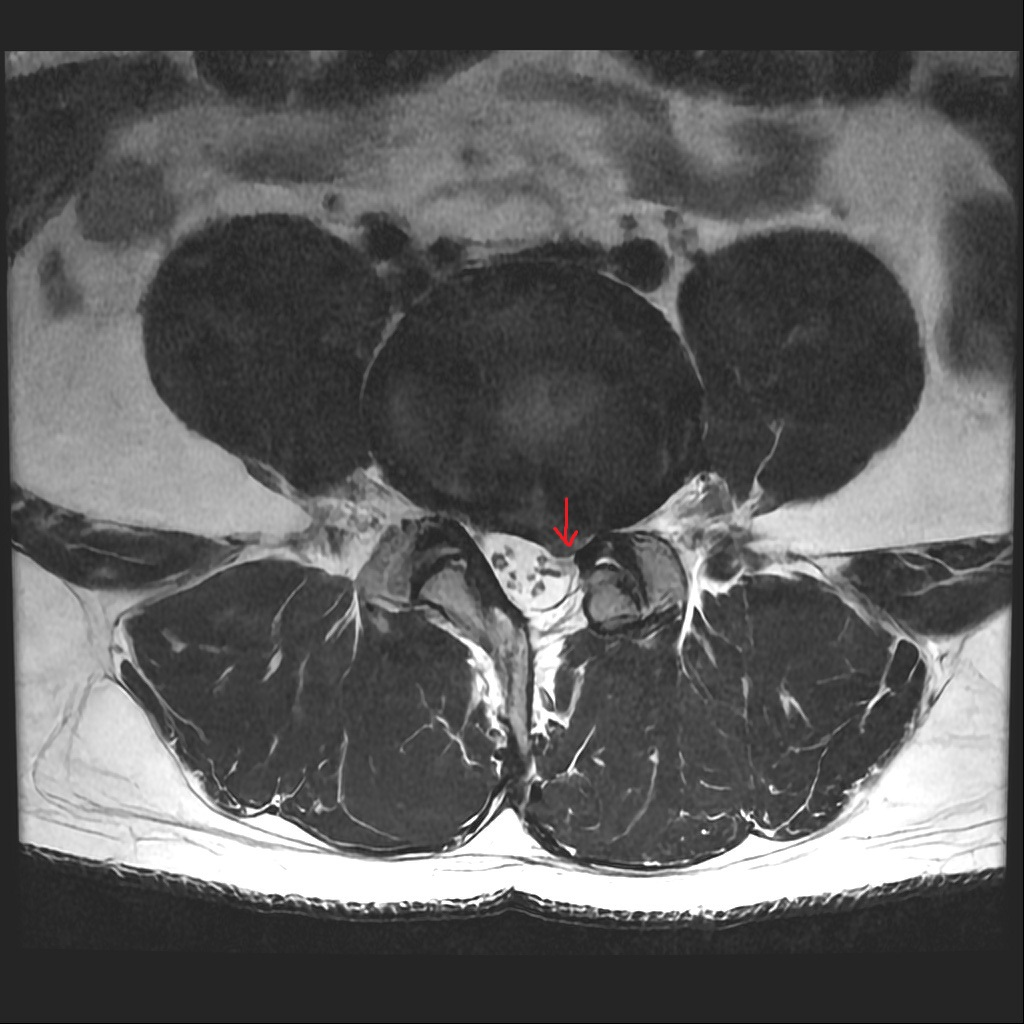

올려주신 MRI 사진상 4번-5번 요추의 디스크 탈출이 있고, 신경도 누르고 있는게 의심됩니다.

올려주신 mri 와 근전도 소견을 종합하면 좌측 L5 신경근이 심하게 압박받고 있으며 신경 손상 증거가 나타납니다.